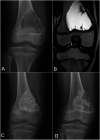

Background: Benign bone cysts in children have a high risk of recurrence after bone grafting. The optimal treatment and filling material for these lesions are currently unknown.

Methods: We compared cyst recurrence after intralesional curettage and filling with allograft versus bioactive glass (BG-S53P4; Bonalive) in a randomized clinical trial. The volume of recurrent cyst at 2-year follow-up was the primary outcome.